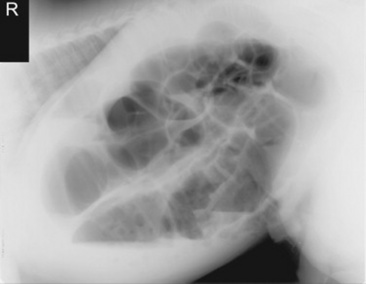

Abdominal radiography is useful to evaluate the small and large intestines for sand accumulation, enterolithiasis, impactions, or small intestinal disorders in foals. When sand is ingested, it generally will accumulate within the large colon along the ventral abdomen8 (Fig. 32-4). Radiography has been found to be a useful method to monitor the resolution of sand impactions after medical management; however, sequential examinations are needed to verify that the volume of sand has reduced.8 If the volume of sand is large enough, it is difficult to determine if an enterolith is present because of summation of the two lesions. Enteroliths are a solid concretion of mineral that usually forms around a nidus, such as a metallic foreign body (Fig. 32-5). The mineral composition is varied, as illustrated by the different opacities present within the enterolith. Radiographs have a 96.4% positive predictive value to detect enteroliths in high-prevalence areas. These enteroliths were generally found to be within the midabdominal radiograph, and 67% of small colon enteroliths caused large colon distention, which was also identified on radiographs.7 Impactions are more difficult to diagnose because usually there is just increased feed accumulation within the abdomen. Although no enterolith or obstruction is identified, granular material can be seen, usually within the ventral colon near the sternal flexure. This is because pelvic flexure impactions will cause the feed material to accumulate orad, causing distention of the left ventral colon (Fig. 32-6). Intestinal disorders such as functional ileus secondary to enteritis (Fig. 32-7) or obstruction secondary to intussusception or meconium impaction (Fig. 32-8) in foals can also be identified on abdominal radiographs. These images show large dilation of the small intestine, and differentiation between functional and mechanical ileus in foals is generally based on the size of the intestine and the volume of gas that is present.9 Evaluation of the abdomen using ultrasound may aid in qualifying the small or large intestinal motility as well as identifying the source of an obstruction if the determination on radiographs cannot be made.

image

Fig. 32-7 Standing lateral radiograph of a 1-day-old, premature quarter horse filly. Note the large amount of gas-distended intestine. Because of the large amount of small intestinal distention, functional ileus is the primary differential diagnosis.